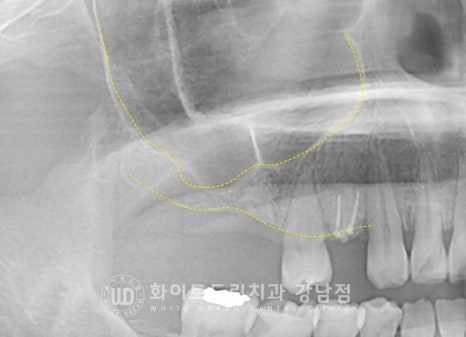

▲ 상악동 거상술 & 임플란트 수술 후 (23.03.07)

상/하악으로 나누어 수술을 진행하는 것보다

오른쪽, 왼쪽으로 나누어 수술을 진행하는 것이

환자분이 식사하기 더 편하실 것으로 판단되어

2회로 나누어 임플란트 식립을 진행하였습니다.

오른쪽 상악 : 23.03.07 / 왼쪽 상, 하악 : 23.03.20

많은 양의 뼈이식이 동반되었기에

충분히 임플란트가 유착될 수 있도록 회복 기간을 넉넉히 잡기로 했습니다.

환자분은 수술 후 5개월의 회복 기간을 가진 후

임플란트 보철 제작 & 세팅에 들어가게 되었습니다.